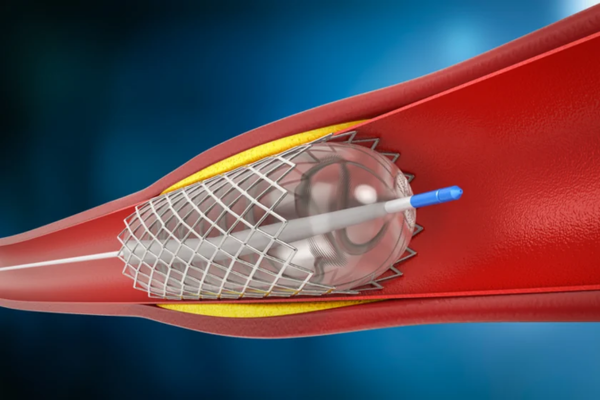

Stent or balloon assisted coiling is used for wide-neck brain aneurysms where simple coiling is unsafe or insufficient. These techniques support the aneurysm neck during treatment.

They help keep coils securely in place, prevent coil movement, and improve long-term aneurysm sealing safely.

Intracranial stenting treats severe narrowing of arteries located within the brain that can cause recurrent strokes or reduced cerebral blood flow.

The procedure widens the affected vessel, improves circulation, and lowers the risk of further ischemic events in carefully selected patients.